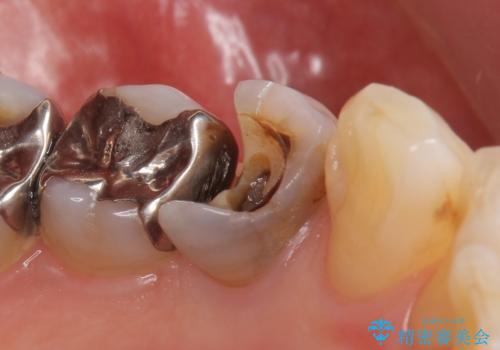

- 他院にて左下4の根管治療を行っていたが、疼くような痛みが引かないため当院にいらっしゃった方の症例です。

左下4の再根管治療を行い症状が治まったのち、オールセラミッククラウンによる補綴を行いました。